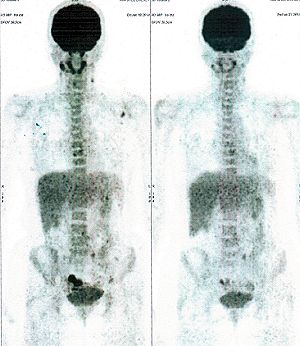

CASE NO: 1 - A FEW MONTHS LATER

A few months after successful treatment for hepatocellular carcinoma, and partially successful for stomach cancer, the PET/CT scan showed the stomach cancer becoming very active, with several metastases to the parts of the liver not previously involved by hepatocellular carcinoma. After a few treatment, all the active stomach cancer lesions in the stomach and in the liver went into remission.